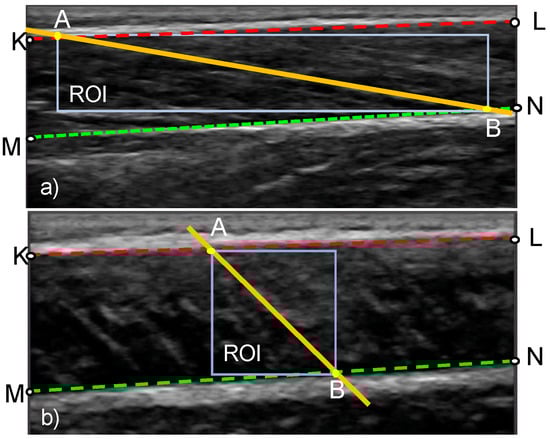

In stage 3, the change in orientation of the fascicles is calculated based on the distortion of a region of interest (ROI) within the fascicle band. The ROI is a rectangle defined by the two insertion points of the fascicle direction line to the aponeurosis lines (points A and B in Figure 5). Once the ROI is defined in the reference frame, the KAZE interest points are identified and tracked in the following frame (tracked frame) using the Kanade–Lucas–Tomasi (KLT) algorithm. To enable the analysis of videos of rapidly changing fascicle direction and length, the ROI is updated and new KAZE interest points defined every two frames throughout the duration of the video (Figure 2). The tracking process is implemented in MATLAB using the pointTracker function. This function uses the optical flow vector (given by the KLT algorithm) to determine the movement of interest points between two frames. Once the new and the old positions of interest points are in hand, the translation (along x-direction and y-direction), rotation, scale (along x-direction and y-direction) and shear/distortion (affine matrix, 6 degrees of freedom) of the ROI is estimated using the estimateGeometricTransfrom2D function in MATLAB. The new position of the fascicle direction line in the tracked frame is found by applying the affine matrix given by the estimateGeometricTransform2D function over the coordinates of the fascicle direction line in the reference frame. Once the analysis of the first two frames is complete, the tracked frame becomes the new reference frame and the entire process is repeated (Figure 2).

Figure 5.

Definition of the region of interest (ROI) in an ultrasound image of a muscle at rest (a) and during maximal contraction (b). The geometric points that are used in the calculation of FL and PA are also shown. Lines KL and MN, respectively, correspond to the top and bottom boundary of the fascicle band. Points A and B denote the insertion points of the fascicle direction line.

2.4. Stage 4: Calculation of PA and FL

After obtaining the new position of the fascicle direction line and the boundaries of the fascicle band, the insertion points of the fascicle direction line (points A and B in Figure 5) are determined, followed by the computation of FL as their Euclidean distance. PA is calculated as the angle between the fascicle direction line and the deep aponeurosis (angle ABM in Figure 5).